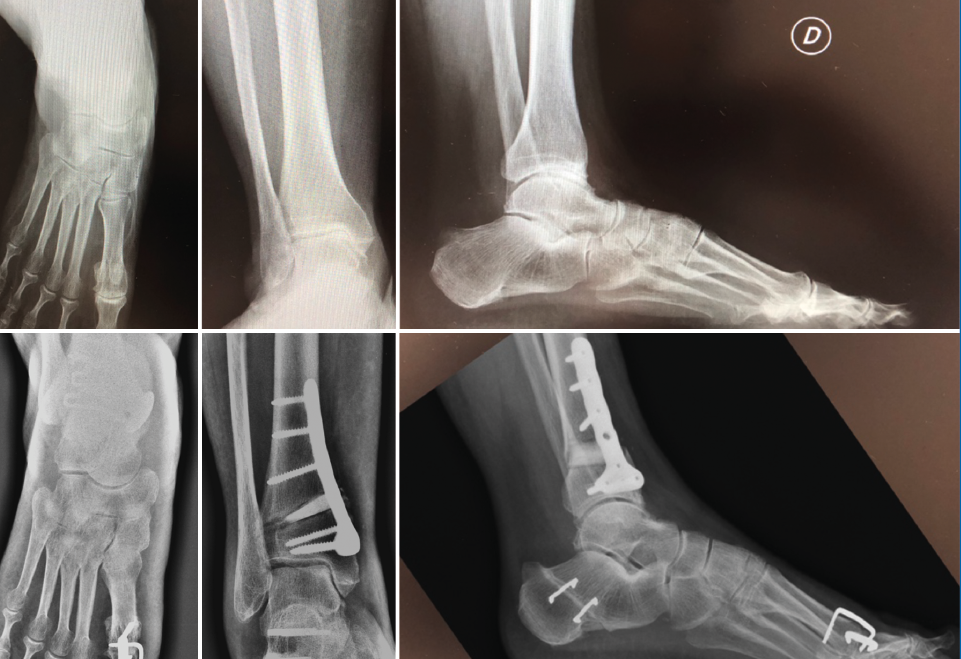

Hay que tener en cuenta que las intervenciones supramaleolares pueden ser suficientes, insuficientes o incluso cambiar una “adecuada” alineación previa del retropié en el proceso de buscar un nuevo equilibrio de las fuerzas de carga. Por esto, siempre hay que tener en consideración la necesidad de procedimientos inframaleolares. Más aún, existen situaciones en las cuales se podría considerar solo una intervención inframaleolar si el caso en particular lo permite. También se pueden identificar presentaciones atípicas de desaxación, aunque menos frecuentes en general, como lo son las deformidades en plano valgo con una interlínea de tobillo en varo. En estas situaciones las actuaciones supra- e inframaleolar serán de sentido inverso (Figura 3).

Figura 3. Malalineaminento en varo tobillo-valgo subtalar (osteotomía –OTT– supramaleolar –SM– de apertura más OTT de calcáneo varizante).